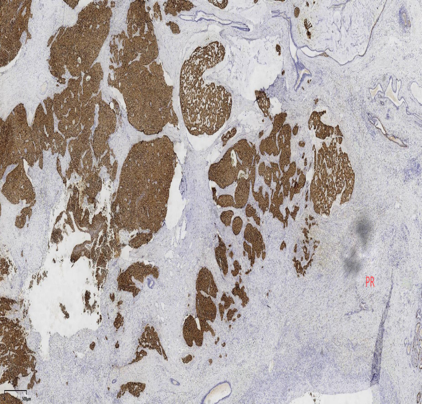

免疫组化

ER弥漫强+,Her2-,ki67低表达

具有神经内分泌表达:CgA、Syn(约70%的比例,阳性细胞表达不等)

CK5/6、CKH-,可斑驳性的残留

肌上皮内-,导管周可-可+